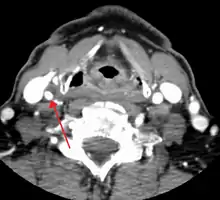

One of several different imaging modalities, such as a computed tomography angiogram (CTA)[12][13][14] or magnetic resonance angiogram (MRA) may be useful. Each imaging modality has its advantages and disadvantages - Magnetic resonance angiography and CT angiography with contrast is contraindicated in patients with chronic kidney disease, catheter angiography has a 0.5% to 1.0% risk of stroke, MI, arterial injury or retroperitoneal bleeding. The investigation chosen will depend on the clinical question and the imaging expertise, experience and equipment available.[15]

For purposed of treatment, the degree of carotid stenosis is defined as:

- percent stenosis = ( 1 − ( minimum diameter within stenosis) / ( poststenotic diameter ) ) × 100%.